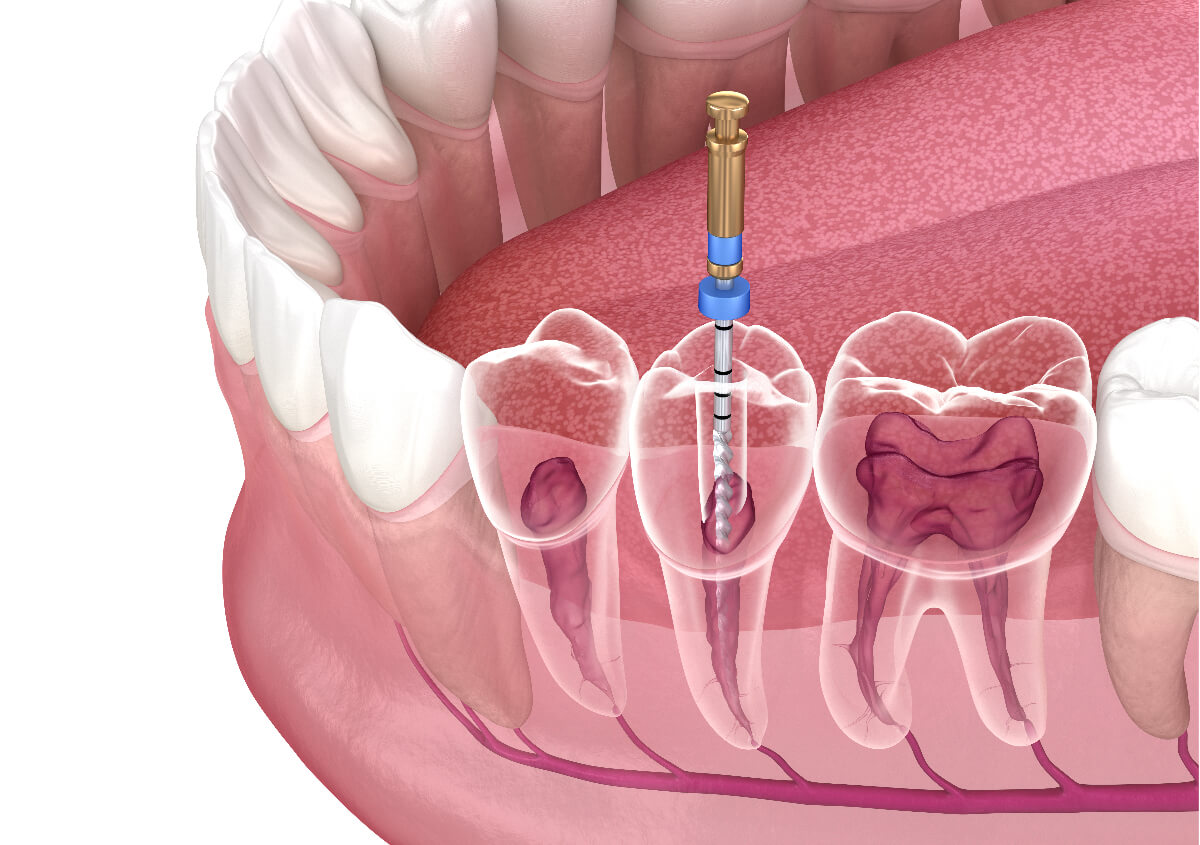

- Root Infections - Identifying abscesses or infections at the tooth's root.

Beyond diagnosis, regular imaging plays a vital role in treatment planning. Whether you're considering braces or implants or undergoing root canal therapy, precise images enable personalized care tailored to your unique anatomy.

Dental x-rays also serve as a critical tool in planning complex dental treatments such as orthodontics, implants, and extractions. The detailed imagery helps create precise treatment plans tailored to each patient's unique anatomy. To explore how modern technology is shaping these plans, visit our page on digital dentistry benefits.